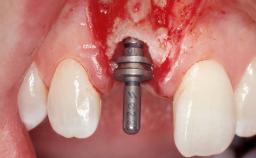

A 30-year-old female patient had lost tooth 21 and was referred to our clinic for consultation and treatment. Due to advanced apical infection, tooth 21 had been extracted two months earlier at another clinic and an acrylic-resin tooth had been bonded to the adjacent teeth. The patient desired implant treatment to avoid any damage to the adjacent natural teeth. While the patient had no history of any systemic disorder, she was a heavy smoker and exhibited medium to advanced periodontitis in the entire jaw. After the initial treatment to achieve a pocket probing depth of less than 4 mm and no bleeding on probing, a decrease in the height of the papillae mesial and distal to the extraction site and overall gingival recession were observed.

Type of Implants One-Piece|Reduced-Diameter

Bone Augmentation Horizontal|Staged

Augmentation Materials Autogenous chips|Membrane

Soft Tissue Grafting Simultaneous

Placement Protocol Early or late implant placement

Bone Volume Deficient horizontally, requiring prior grafting